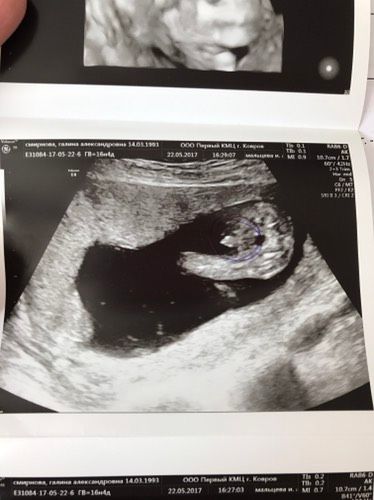

Девченки, узи делала в 16 нед и 4 дня) пацан же??? А то чет сейчас перед 2 скринингом сомнения лезут в голову, хотя тут вроде очевидно…